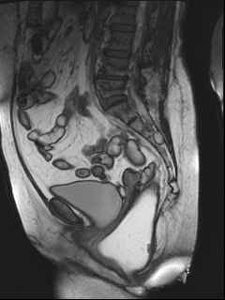

Sagittal late evacuation view shows a cystocele in the middle and posterior pelvic floor compartment. Image courtesy of Dr. Steve Halligan.

Pelvic floor disorders may be difficult to diagnose and are usually evaluated by combining different clinical and radiological investigations, explained Dr. Francesca Maccioni of the department of radiological science at the University "La Sapienza" in Rome. Dynamic MRI has emerged as an alternative method of imaging in the evaluation and understanding of disorders of the pelvic floor, due to its multiplanar capability, high soft-tissue contrast and adequate temporal resolution.

Speakers at Friday's session discussed how MRI can demonstrate the main dysfunctions of the posterior pelvic floor, and also outlined current clinical indications and implications of dynamic MRI of the pelvic floor. A major advantage of MRI is that it provides a unified view of the pelvic floor, and diseases of the anterior, middle, and posterior pelvic floor compartment can be adequately assessed in a single examination. It can also help to reduce examination time, costs, and patient discomfort, but importantly it provides a highly accurate and noninvasive evaluation of a unitary system that is often assessed and treated separately. Furthermore, because dynamic MRI offers a complete evaluation of the posterior anorectal compartment and of the anterior and middle compartments, urogynecologists and proctologists can be assisted with their clinical diagnosis, according to Maccioni.